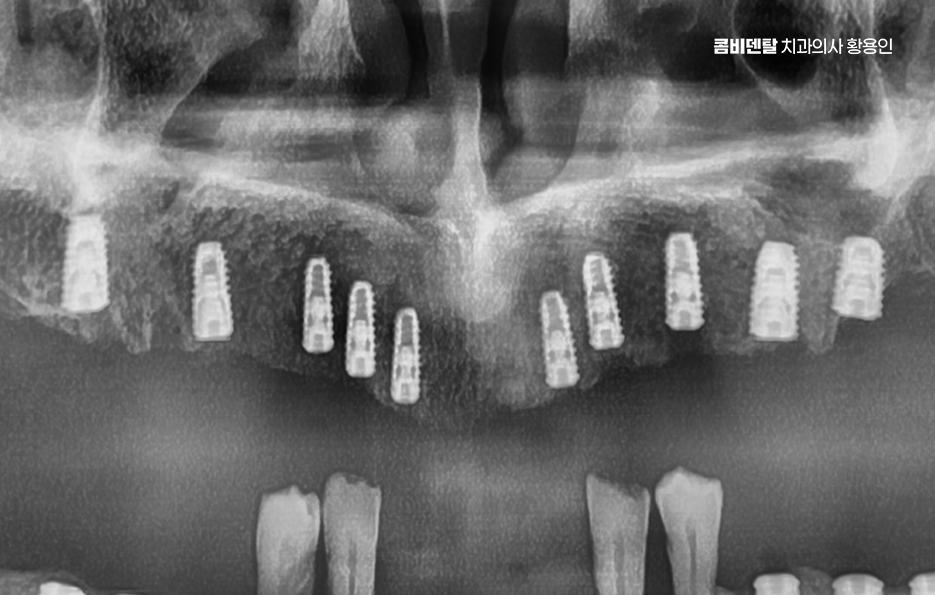

전체 임플란트를 한다고 해서 꼭 치아의 상실 개수만큼 1:1로 임플란트를 심는 건 아니며 보통 무치악인 경우에는 6개에서 8개 정도의 임플란트를 일정한 간격으로 심고, 그 위에 여러 개의 치아가 연결된 브릿지 형태의 보철물을 올리는 방식으로 치료를 하며 환자의 경제적인 부분 부터 잇몸 뼈의 상태에 따라 임플란트의 식립 개수는 다소 차이가 있어요

예를 들어 잇몸 뼈가 충분히 있는 경우에는 임플란트를 더 많이 심어서 지지력을 높이고, 잇몸 뼈가 많이 줄어든 경우에는 임플란트의 식립 개수를 최소화 하는 방식으로 치료 방법이 달라지는 것이며 경우에 따라서는 임플란트 틀니 처럼 임플란트와 틀니의 중간 지점의 선택지를 활용하는 경우도 있어요